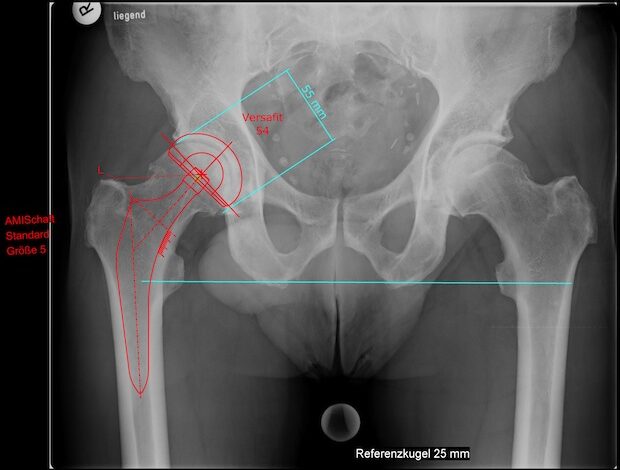

Winterberg - Die Hüftoperation von vorne nach der AMIS-Methode wird bereits seit vielen Jahren in der international renommierten Universitätsklinik in Zürich durchgeführt. Internationale Spezialisten haben seit Jahren viele tausend Patienten…